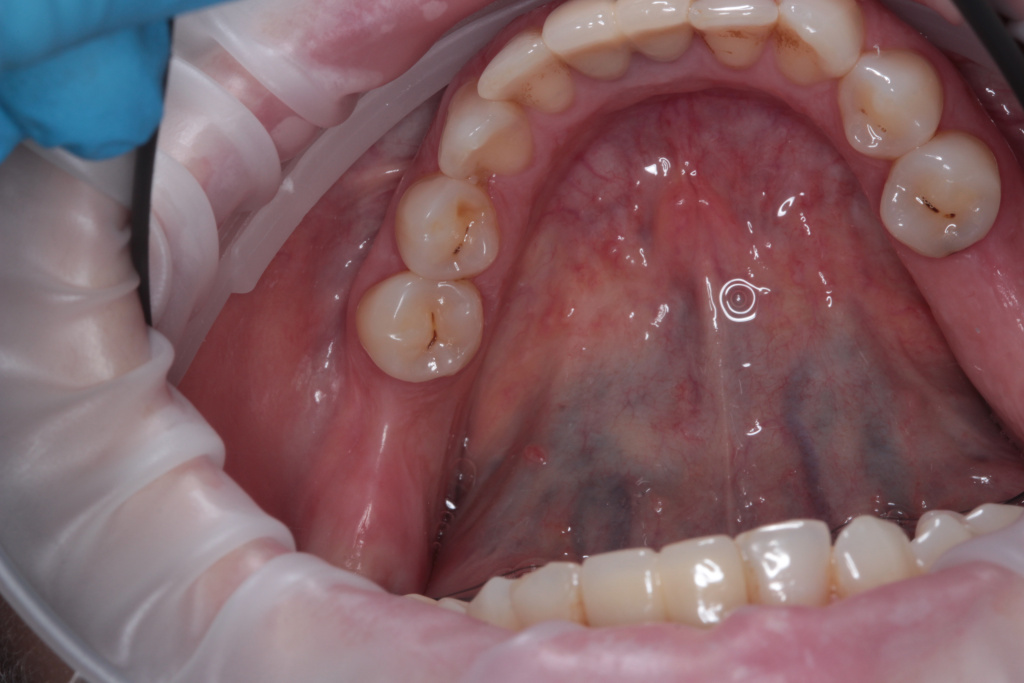

Описание клинического случая:

Клинический случай Узденовой Зульфы Альбертовны